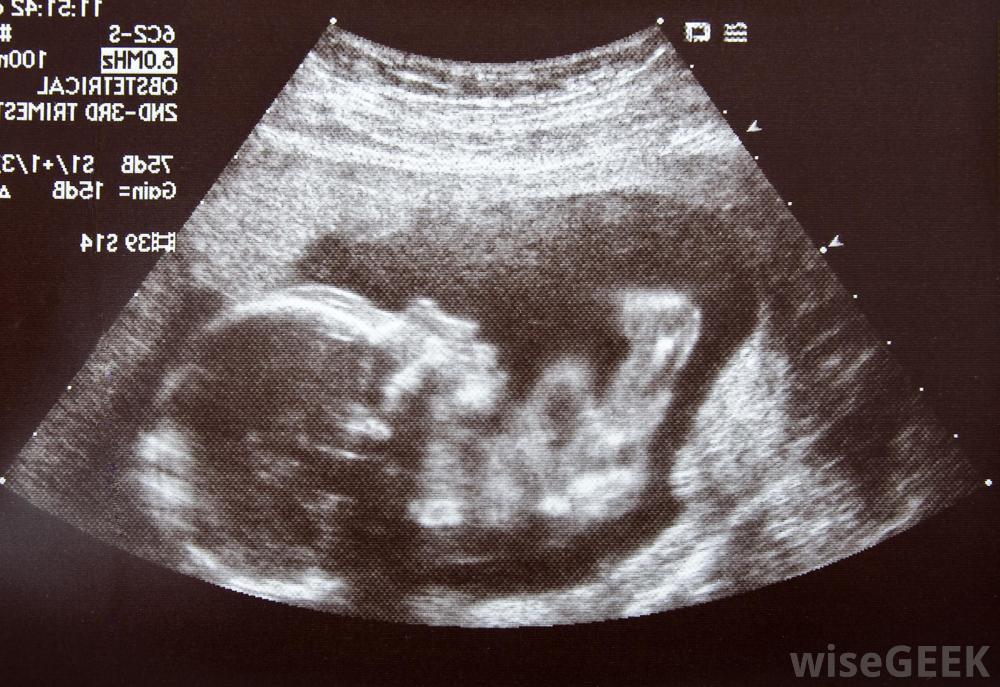

超声波可以跟踪胎儿在子宫内的发育过程一旦卵子受精,它会促使女性的身体产生高于正常水平的激素,包括雌激素和孕酮,这些激素帮助身体做好准备,支持婴儿的成长例如,它们在帮助保持子宫内膜的厚度以保护发育中的胚胎以及胎盘的发育中发挥作用,这是胚胎氧气和营养的主要来源。